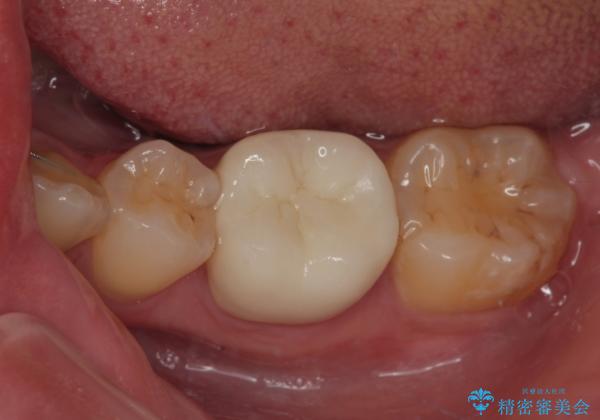

- 当院で矯正治療を終えて、左下が虫歯になっている気がするとのことで来院された患者様です。レントゲン検査の結果、コンポジットレジンによる修復箇所が複数行われており、詰め物の下に虫歯を認めました。

拡大鏡視野下でコンポジットレジン、虫歯の除去を行い、オールセラミッククラウンに適した形に整えました。

虫歯による不快な症状がなくなり喜んでいただきました。セラミックの被せものが入った後の違和感なく過ごせているそうです。矯正治療終了直後の被せもの治療なのでリテーナーの作成回数をできるだけ少なく迅速に行うことを考慮して治療を行いました。

今後、ホワイトニングを行う予定なので、患者様のご希望により、周りの歯に比べてあえて白い被せものを作成しました。